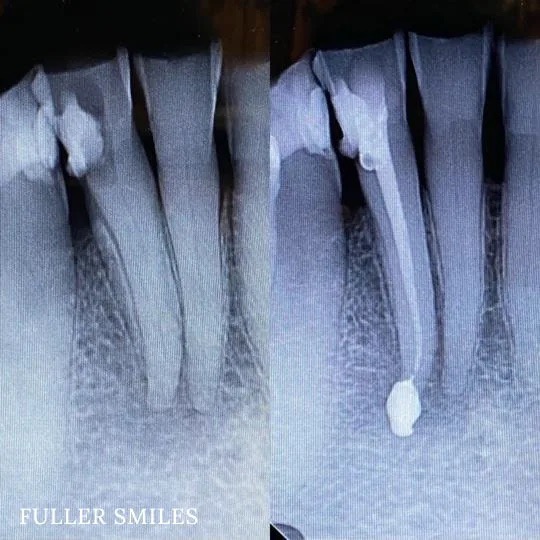

Patient presented to the office with trauma to front two teeth several weeks ago causing her severe pain. After a thorough clinical exam which included endodontic screening and proper x rays led to the diagnosis of necrotic (dead) pulp tissue due to the force of trauma.

Root canals were performed and highly aesthetic Emax crowns were fabricated to meet the patient’s desire to maintain the natural smile and contour as was before the trauma.